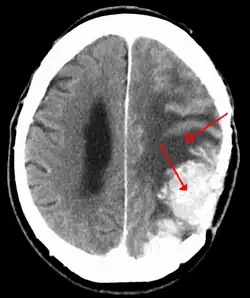

Meningiomas are visualized readily with contrast CT, MRI with gadolinium,[23] and arteriography, all attributed to the fact that meningiomas are extra-axial and vascularized. CSF protein levels are usually found to be elevated when lumbar puncture is used to obtain spinal fluid. On T1-weighted contrast-enhanced MRI, they may show a typical dural tail sign absent in some rare forms of meningiomas.[18]

Although the majority of meningiomas are benign, they may have malignant presentations. Classification of meningiomas are based upon the WHO classification system.[24]